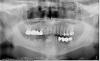

161616 Опубликовано 8 июля, 2010 Поделиться Опубликовано 8 июля, 2010 Вообщем, есть вот такая челюсть (моя :-) с мостами, дышащими на ладан (думаю, что их надо убирать). http://s16.radikal.ru/i191/1007/04/d64ef4b5c33e.jpgЗадача: по уму поставить где надо импланты, коронки (где лучше поставить именно их), чтобы о теме зубов забыть очень надолго (в идеале на всю жизнь. А жить я планирую долго :-) ). О себе, мужчина, 43 года, известных мне проблем со здоровьем, аллергий нет.Живу в Зеленограде (Москва), хотелось бы найти качественного врача (клинику) в радиусе разумной территориальной доступности. Приоритет отдается больше качеству и гарантиям, чем минимальной цене. Нужен будут полный набор официальных бумаг (чеки, договора и все такое). Желательно минимальное количество визитов в клинику (но не в ущерб качеству). Нужны будут временные протезы на время периода установки имплантов. Если готовы взяться за эту задачку (или есть кому грамотному меня посоветовать), то жду предварительное предложение в личку или по 163264128@мылору, что нужно делать с этим кошмаром, сколько это примерно стоит, какие будут этапы, какие гарантии и прочая полезная для принятия решения инфа. Если есть доп. вопросы - спрашивайте. Спасибо за внимание. Ссылка на комментарий

161616 Опубликовано 8 июля, 2010 Автор Поделиться Опубликовано 8 июля, 2010 (изменено) План лечения (пока по снимку, без посещения живьем) и цены. Фото плана лечения http://s46.radikal.ru/i112/1007/28/eb381664ec9e.jpg 1 ЭТАПудаления зубов, наращивание костной ткани на нижней челюсти с обеих сторон - 80000р 2 ЭТАП (через 2 мес)синус лифтинг с двух сторон + установка 4 имплантатов - 80000+ 140000 (если Nobel Replace они по 35, если Tit Fix - 25000 X 4) = 220000р 3 ЭТАП (через 2 мес)установка 7 имплантатов на нижней челюсти 35000 X 7= 245000р 4 ЭТАП (через 3 мес)постоянное протезирование на нижней челюсти - 150000р (если на Nobel Replace) 5 ЭТАП (через 1 мес)постоянное протезирование на верхней челюсти - 85000р (если на Nobel Replace) Итого: 780 000р в течении 8 мес С другими имплантатами будет другая цена, возможны скидки, надо обговорить с администрацией.Оплата производится по факту в зав. от проделанной работы. Подсчеты проделаны по максимуму, сумма может быть значительно меньше. Исходная задача: Вообщем, есть вот такая челюсть (моя :-) с мостами, дышащими на ладан (думаю, что их надо убирать). http://s16.radikal.ru/i191/1007/04/d64ef4b5c33e.jpgЗадача: по уму поставить где надо импланты, коронки (где лучше поставить именно их), чтобы о теме зубов забыть очень надолго (в идеале на всю жизнь. А жить я планирую долго :-) ). О себе, мужчина, 43 года, известных мне проблем со здоровьем, аллергий нет.Живу в Зеленограде (Москва), хотелось бы найти качественного врача (клинику) в радиусе разумной территориальной доступности. Приоритет отдается больше качеству и гарантиям, чем минимальной цене. Нужен будут полный набор официальных бумаг (чеки, договора и все такое). Желательно минимальное количество визитов в клинику (но не в ущерб качеству). Нужны будут временные протезы на время периода установки имплантов. Изменено 8 июля, 2010 пользователем 161616 Ссылка на комментарий